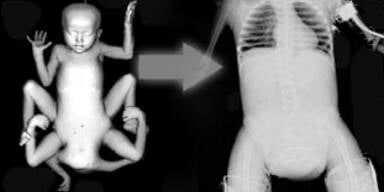

Die zweijährige Lakshmi ist mit vier Armen und vier Beinen auf die Welt gekommen. Die Operation ist erfolgreich abgeschlossen worden.

In einer 24-stündigen Operation haben indische Chirurgen ein zweijähriges Mädchen von einem angewachsenen Zwilling ohne Kopf getrennt und lebenswichtige Teile ihres Körpers wiederhergestellt. "Sie hat die Operation überstanden, sie ist in Sicherheit und es geht ihr gut", sagte Chef-Chirurg Sharan Patil über Lakshmi, die mit vier Armen und vier Beinen geboren worden war.

Die indischen Mediziner präsentierten voller Stolz Röntgenbilder der äußerst schwierigen aber erfolgreich verlaufenen Operation.

Das Mädchen Lakshmi ist nach der vierarmigen indischen Gottheit für Wohlstand und Schönheit benannt. Lakshmi sei ein sehr seltener Fall einer Verschmelzung, die nur bei zwei Prozent aller Siamesischen Zwillinge vorkomme, sagte die Koordinatorin der Sparsh-Stiftung, Mamatha Patil. Einer der Zwillingsembryonen höre im Mutterleib auf zu wachsen, und der andere entwickele sich auf dessen Kosten. Die vier zusätzlichen Gliedmaßen gehörten dem zweiten unterentwickelten Körper und seien an Lakshmis Beckenknochen angewachsen, erläuterte Patil weiter.

36 Ärzte an OP beteiligt

An der Operation waren 36 Ärzte beteiligt, vom Kinderarzt bis zum plastischen Chirurgen waren zahlreiche Fachgebiete vertreten. Im ersten Teil des Marathon-Eingriffs wurden die überflüssigen Körperteile abgetrennt. Im zweiten Teil musste dann das Becken des Kindes wiederhergestellt und Haut wieder angenäht werden. Da zum Beispiel die Niere der Zweijährigen sich teilweise im Körper des Zwillings befunden hatte, musste das Organ verschoben werden.